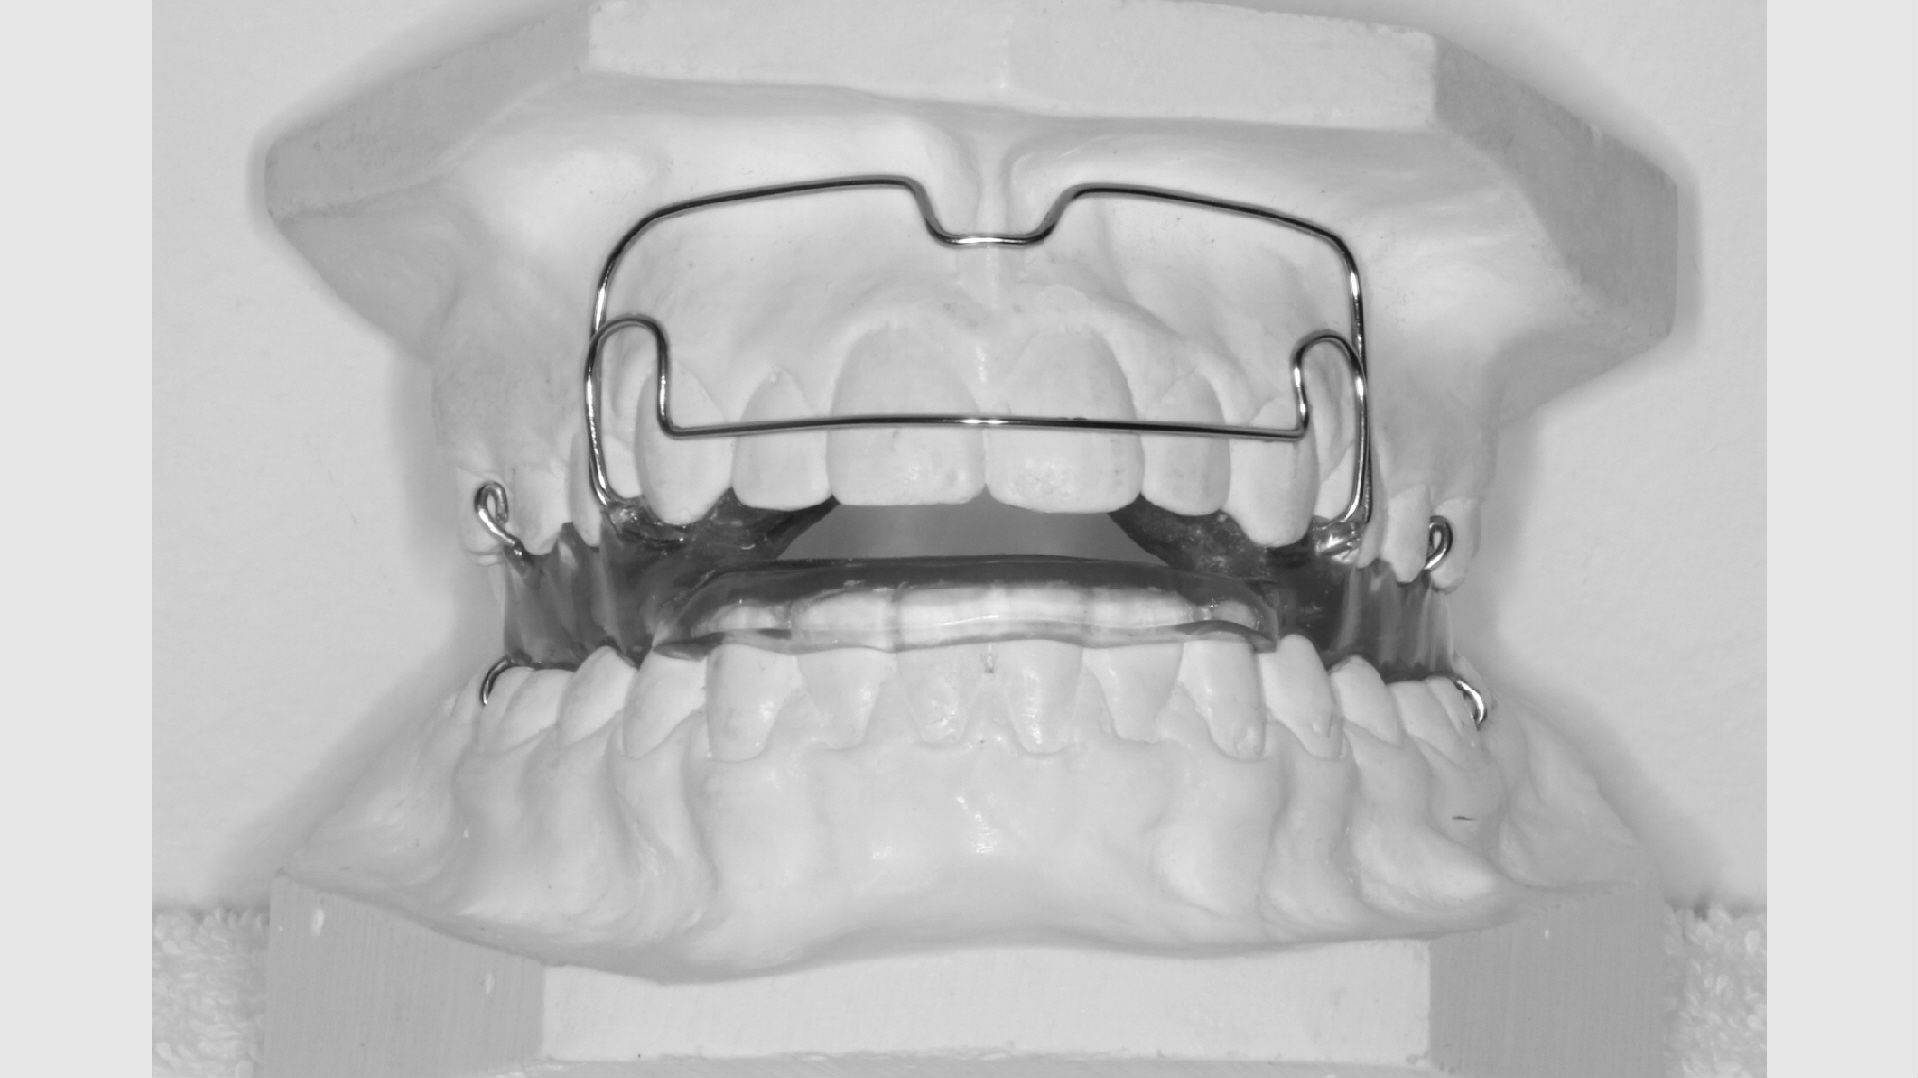

Hvis behandlingen skal gøres med en aftagelig bøjle, får dit barn eventuelt taget aftryk hertil umiddelbart efter samtalen.

Aftagelige bøjler

Nogle tandstillingsfejl kan rettes med bøjler, du selv kan tage ind og ud. For at de skal virke, er det naturligvis afgørende, at du bruger bøjlen på den rigtige måde. Ofte vil det være nødvendigt, at du har bøjlen på i alle døgnets 24 timer - på nær når du spiser og børster tænder. Du vil altid få klar besked om, hvordan og hvor meget du skal bruge din bøjle.